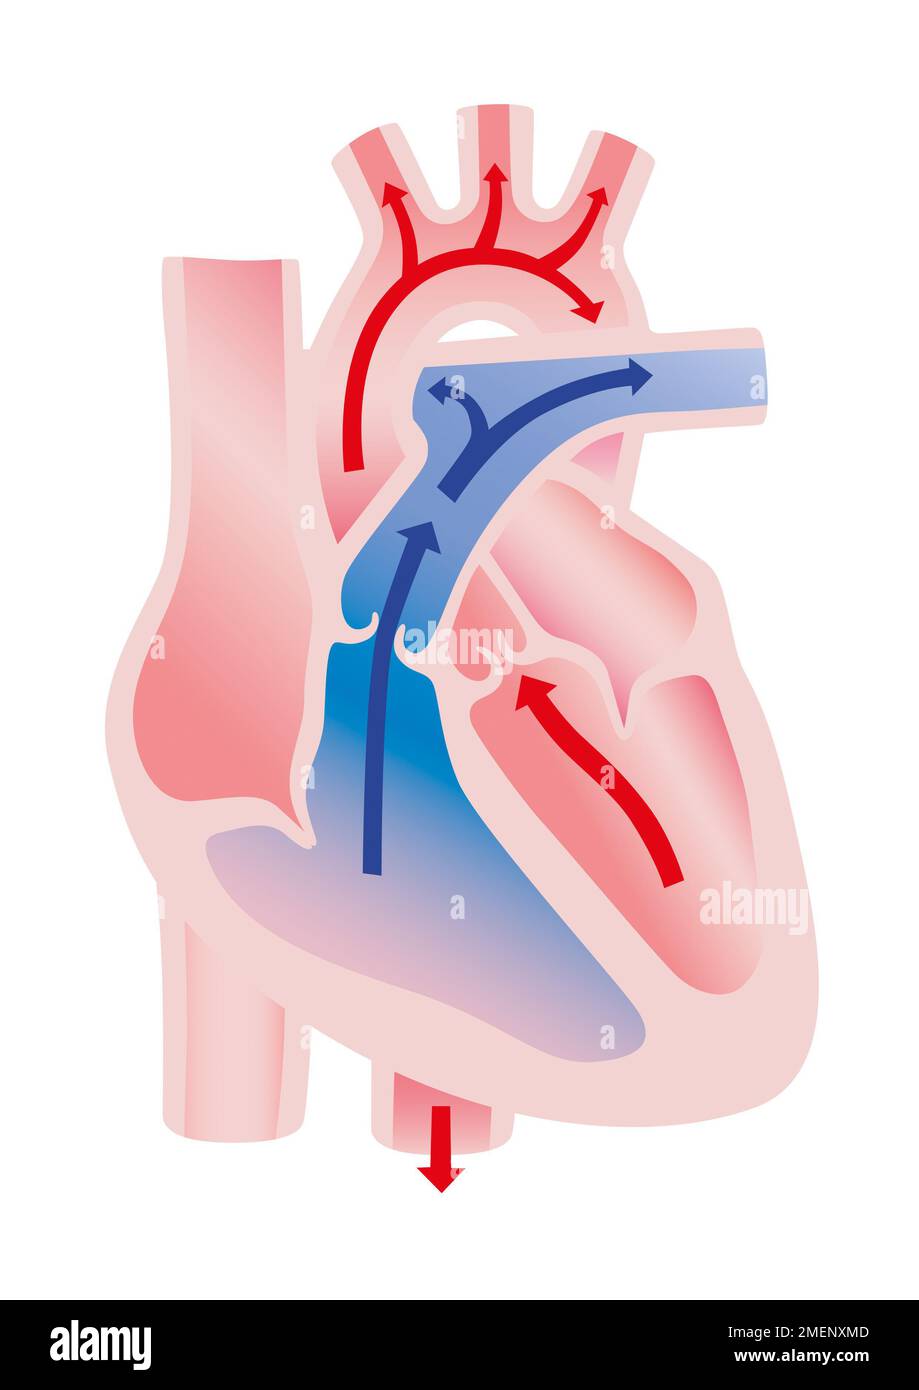

Heart out Final illustration Stock Photohttps://www.alamy.com/image-license-details/?v=1https://www.alamy.com/heart-out-final-illustration-image508187805.html

Heart out Final illustration Stock Photohttps://www.alamy.com/image-license-details/?v=1https://www.alamy.com/heart-out-final-illustration-image508187805.htmlRM2MENXMD–Heart out Final illustration